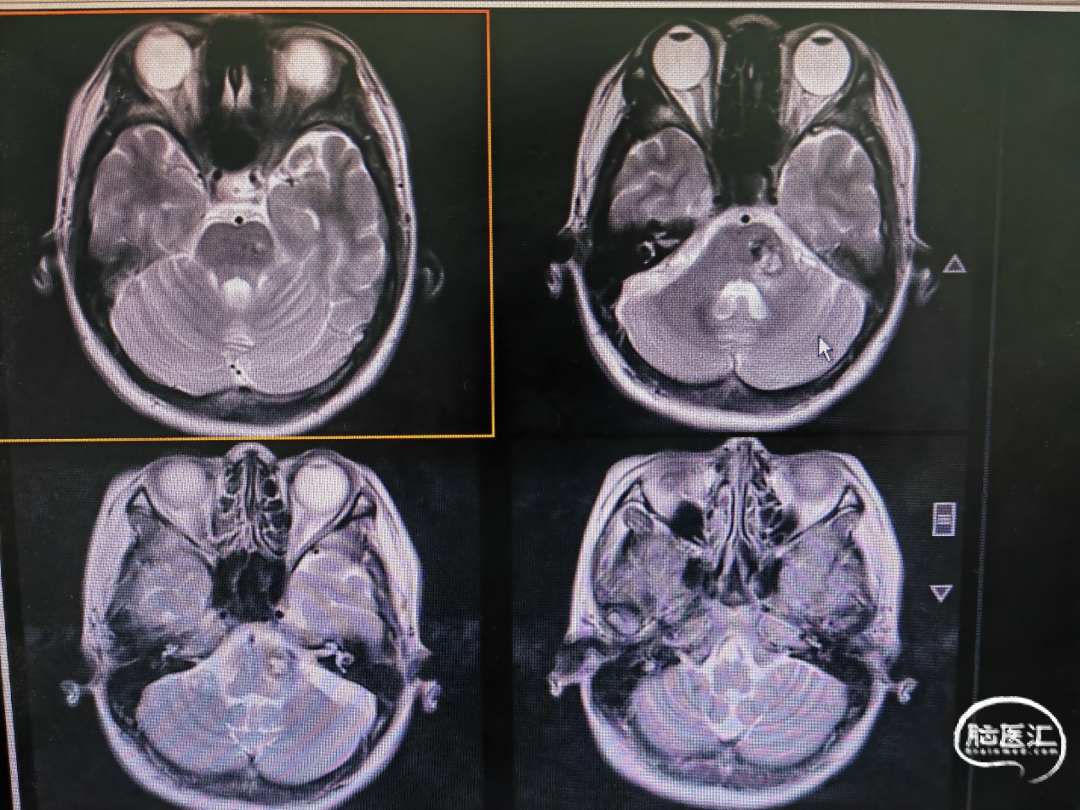

病例一

图2

对于菱形窝型BSCMs,选取枕下后正中入路,俯卧位头部尽量屈曲,沿小脑后下动脉P3段分开扁桃体延髓裂,切开部分下髓帆,右侧暴露相对充足,如果BSCMs未破溃至桥脑背侧表面,需神经电生理明确面丘位置,明确两个安全切入区三角,面丘上三角及面丘下三角,神经导航选择其一进入。

本例患者暴露四脑室菱形窝后已可见明显破溃口,电生理监测破溃点为面丘上三角,予以顺利切除,术后患者无新发神经功能障碍。